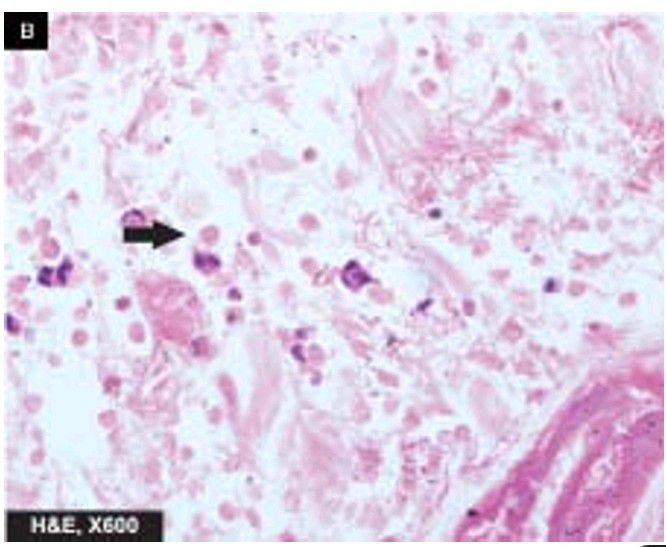

Amoebic ulcers large intestine

Trophozoites of Entamoeba histolytica are seen at the margin of ulcer (arrow).